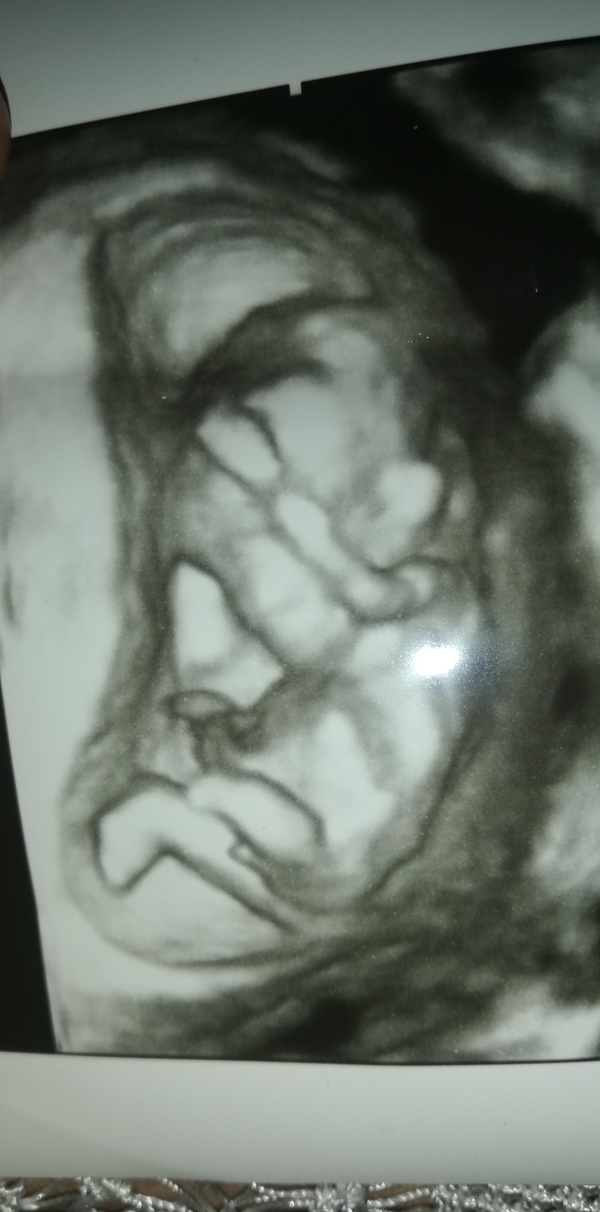

Nub teorisiyle cinsiyet tahmini bebeğim erkek mi kız mı ?

Banada yorum.yapin lutfen 12 haftaligiz

Nub teorsisi için cinsiyet tahmininde yorum isteyen arkadaşlar lütfen uyarımızı dikkate alın. Ultrason görüntüleri elinize ilk verildiği gibi net olmaz. Sık sık ışığa maruz kaldığı için görüntü kalitesi bozuluyor dolaysıyla bizlerde değerlendirme yapamıyoruz. Sizlere yorum yapabilmemiz için görüntü kalitesi aşağıdaki linkte yer alan görseller gibi olmalıdır. Ayrıca Bebeğin cinsiyeti net olarak 18-19-20. haftalarda belli olur..

Merhaba, yüklediğiniz görsellerde nub çıkıntısı anlaşılmıyor , dolaysıyla değerlendirme yapamıyoruz.. Görselin kalitesi aşağıdaki gibi olmaldır.. Sağlıklı gebelik süreci diliyorum.